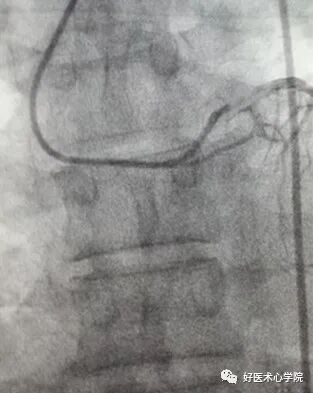

(2)冠脉狭窄程度的测定

计算机辅助的定量分析法(QCA):

以造影导管为参考(通常选用6F造影导管,1F=0.33mm),通过密度法由计算机辅助测定参考血管直径、病变节段直径狭窄百分数和病变长度,推算面积狭窄百分数。

造影导丝是什么珍藏 冠脉造影从流程到诊断,基础必备!_https://www.jmylbn.com_新闻资讯_第82张